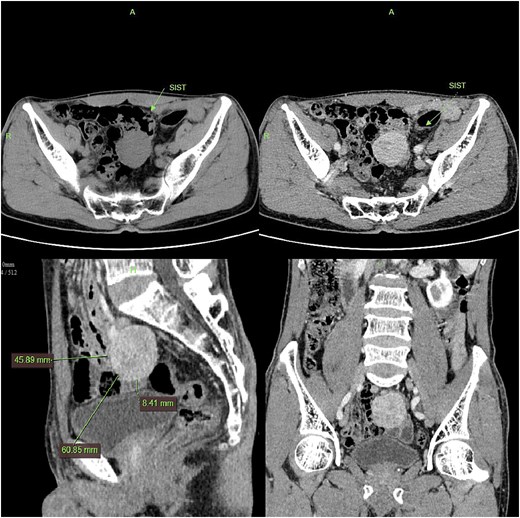

CT imaging shows a pelvic lesion with soft tissue density on non-enhanced scans, marked enhancement of the primary tumor mass after contrast, and coronal/sagittal reconstructions delineating its anatomical location.

Contrast-enhanced CT demonstrated a well-circumscribed, round enhancing mass measuring 4 cm in diameter. Sagittal imaging showed the lesion positioned 0.9 cm from the bladder wall, 4.5 cm from the anterior abdominal wall, and 6.1 cm from the pubic symphysis (Fig. 2). The mass exhibited an intact capsule without evidence of rupture. MRI performed within a 24-hour period, sagittal imaging showed the lesion positioned 7.9 cm from the bladder wall, 1.3 cm from the anterior abdominal wall, and 9.3 cm from the pubic symphysis, and confirmed stable positioning and morphology, maintaining identical spatial relationships to adjacent structures (Fig. 3).